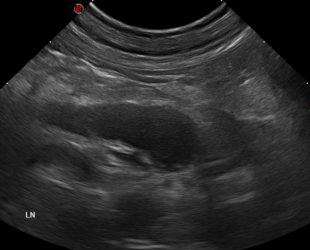

Analíticamente, destaca una anemia normocítica normocrómica no regenerativa con un hematocrito del 20 % (35 – 60 %), trombocitopenia de 43 000 plq/µL (140 000 – 520 000), leucocitosis de 22 860 leuc/µL (5 320 – 16 920), neutrofilia de 16 500 neut/µL (3 050 – 12 100) e hiperglobulinemia de 4,0 g/dL (1,6 – 3,7). En la ecografía abdominal se aprecia una marcada linfadenopatía abdominal generalizada con reacción peritoneal y esplenomegalia homogénea (Figura 1). Se realizan citologías de linfonodos mesentéricos (Figura 2).